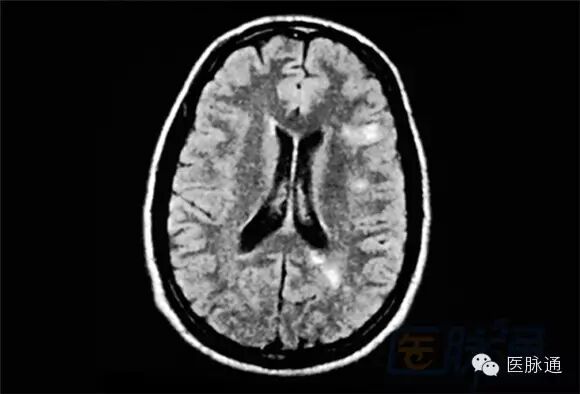

MRI对于评估复发型MS疾病进展是特别有效的。MRI所示为RRMS患者,前面的一张为同一患者3个月以后所做。病变的大小显著减小。